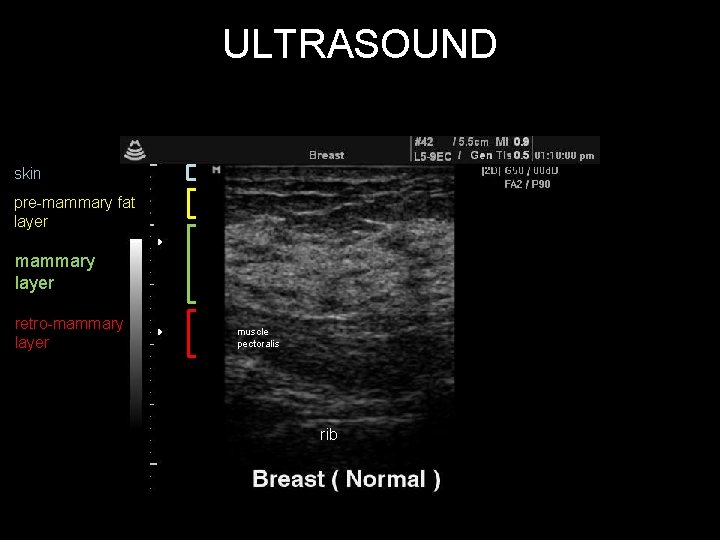

ULTRASOUND • patient positioning: support elbow, flat, supine • probe: linear array 7 -13 MHz

ULTRASOUND skin pre-mammary fat layer mammary layer retro-mammary layer muscle pectoralis rib